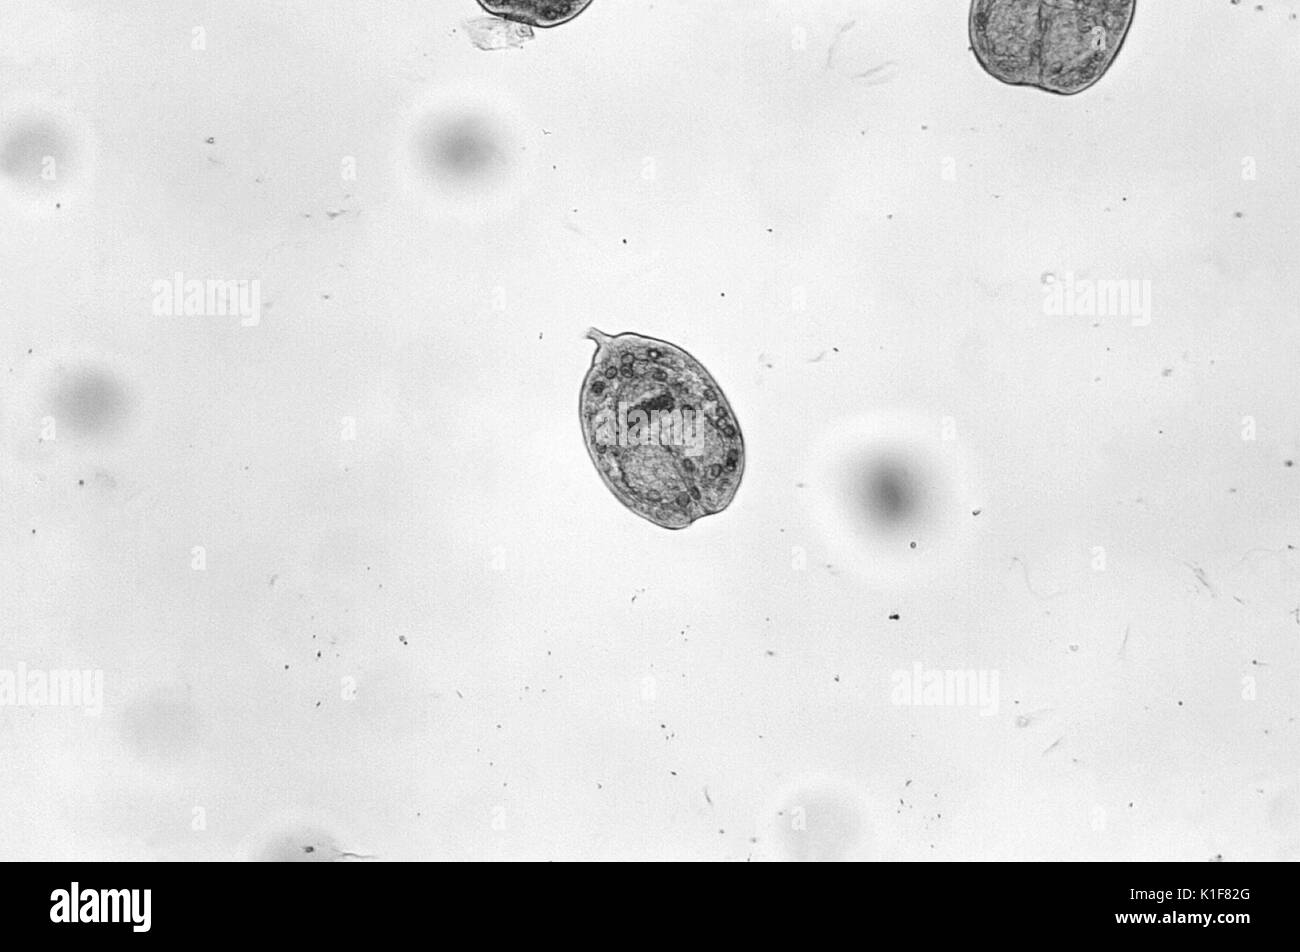

Questo parassita misura allo stadio adulto dai 3 ai 9 mm di lunghezza, ed è composto solamente di tre proglottidi, di uno scolice posto alla testa dotato di quattro ventose e di un rostro centrale, posto sulla punta dello scolice, da cui si dipartono dai 28 ai 50 uncini. Le sue uova sono difficilmente distinguibili da quelli di altre specie di tenie e misurano dai 32 ai 36 micrometri.

Il parassita viene ingerito accidentalmente attraverso alimenti contaminati dalle larve, contenute in capsule che con i succhi gastrici vengono sciolte ed entrano nel sangue a livello dell'intestino. Attraverso il circolo poi si diffondono e vanno a incistarsi in zone vascolarizzate, provocando cisti idatidee. Le cisti più comuni si sviluppano nel fegato e nei polmoni, arrivando anche ad avere le dimensioni di un feto, se si incistano nella cavità addominale. All'interno delle cisti si formano numerosi protoscolici, da cui si svilupperanno nuovi parassiti. Il ciclo si completa quando il cane ingerisce cisti presenti nella carne e nelle frattaglie di animali infetti.